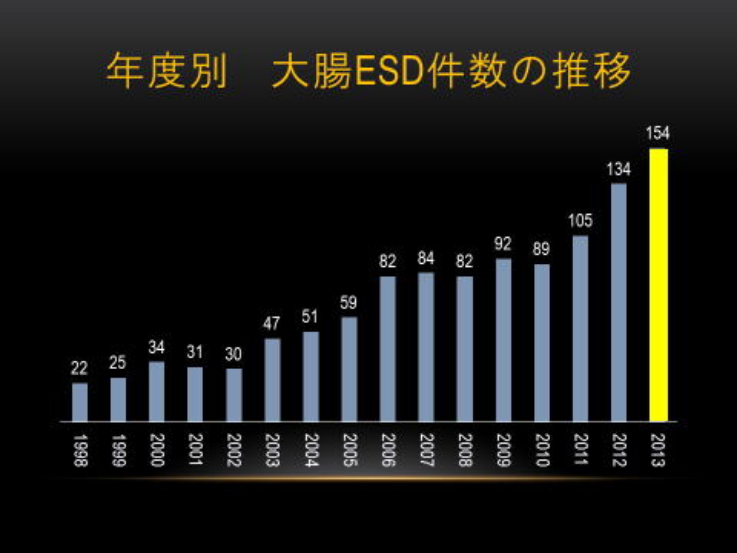

早期大腸癌に対するESD

実績(2020年)

診療実績

| 粘膜切開剥離術 | 100件 | |

ESDの成績 | (100病変) |

|---|---|---|

| 腫瘍サイズ平均 | φ35.2mm | |

| 一括切除率 | 97.0%(97/100) | |

| 出血率 | 2.0%(2/100) | |

| 穿孔率 | 5.0%(5/100) |